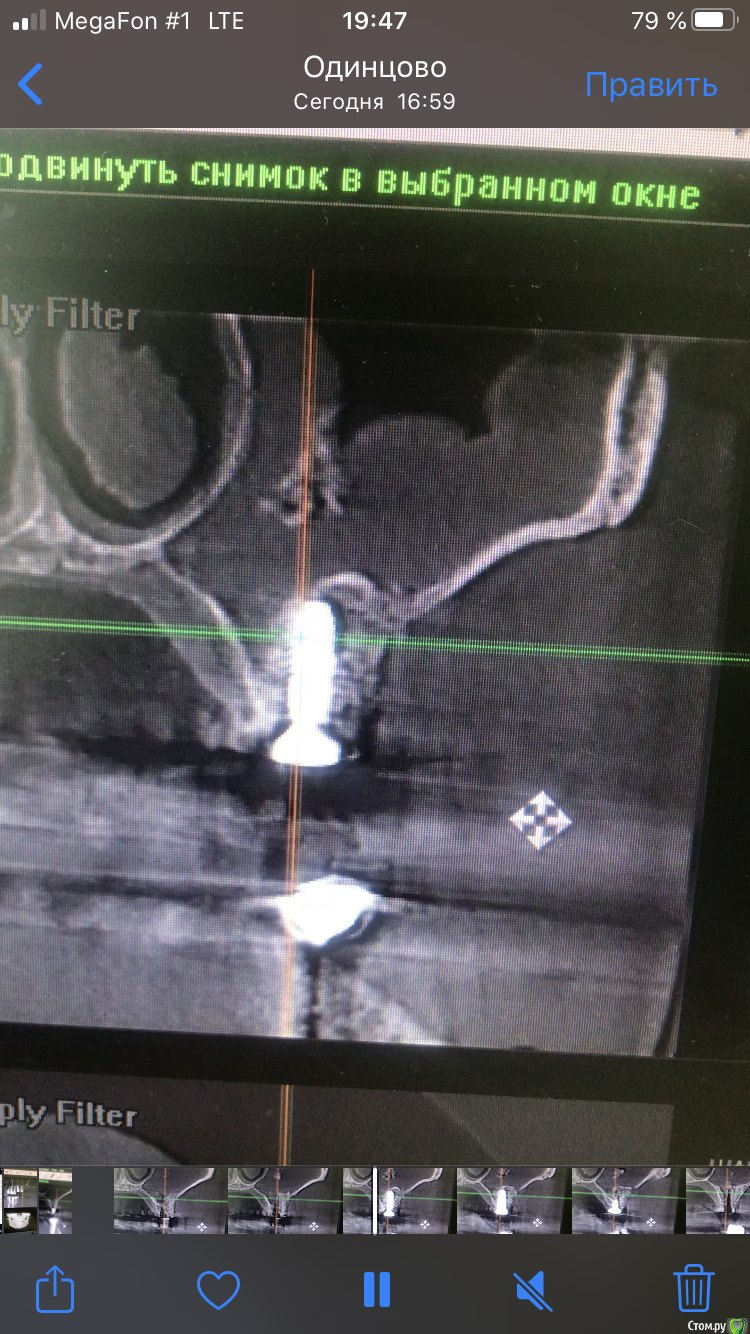

dave09090 Опубликовано 11 августа, 2020 Поделиться Опубликовано 11 августа, 2020 (изменено) Приветствую коллеги. 4-ре мес назад была проведена операция ОСЛ с одномоментной имплантацией . Послеоперационный период прошёл хорошо без болей и выделений. Неделю назад позвонила и сказала что чувствует имплантат при беге или стуке ногой. Поросил сделать кт. И там такое. Перфорацию почему то во время операции не углядел видимо. Что посоветуете делать ? Изменено 11 августа, 2020 пользователем dave09090 Ссылка на комментарий

stommm Опубликовано 11 августа, 2020 Поделиться Опубликовано 11 августа, 2020 Вижу 2 варианта: лор через естественное соустье расширив его убирает свободно лежащий графт. Остальное, если плотное, оставить и дать через пару месяцев нагрузку на имплант времяшкой. Самому сделать доступ повыше, убрать графт и далее все то же самое что и в первом варианте. Если графт вокруг импланта мягкий, то либо ждать еще, либо убирать все 1 Ссылка на комментарий

L.E.S.I.K. Опубликовано 12 августа, 2020 Поделиться Опубликовано 12 августа, 2020 (изменено) Оставлять так в любом случае нельзя?Нет. Графт, лежащий в синусе - инородное тело, и как следствие, будет поддерживать течение воспалительного процесса. Изменено 12 августа, 2020 пользователем L.E.S.I.K. 1 Ссылка на комментарий

Александр07 Опубликовано 13 августа, 2020 Поделиться Опубликовано 13 августа, 2020 Если Имплант стабилен и внешне все норм я бы через Лора эндоскопически, пусть вычистит , а/б, и наблюдать, если не пройдёт тогда уже самому оставшееся проще убрать будет при необходимости Ссылка на комментарий

dave09090 Опубликовано 14 августа, 2020 Автор Поделиться Опубликовано 14 августа, 2020 спасибо. имплантаты стабильны торг проверял 35. Ссылка на комментарий